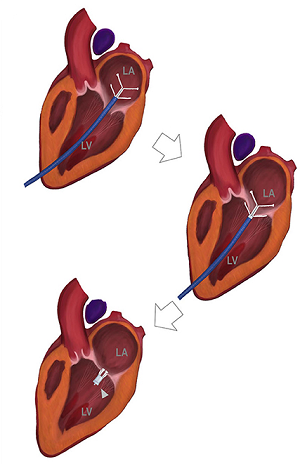

Vertebral Scale System to Measure Canine Heart Size in Radiographs. James Buchanan and Jorg Bücheler. JAVMA January 1995; 206(2): 194-199. Quote: "A method for measuring canine heart size in radiographs was developed on the basis that there is a good correlation between heart size and body length regardless of the conformation of the thorax. The lengths of the long and short axes of the heart of 100 clinically normal dogs were determined with calipers, and the dimensions were scaled against the length of vertebrae dorsal to the heart beginning with T4. The sum of the long and short axes of the heart expressed as vertebral heart size was 9.7 +/- 0.5 vertebrae. The differences between dogs with a wide or deep thorax, males and females, and right or left lateral recumbency were not significant. The caudal vena cava was 0.75 vertebrae +/- 0.13 in comparison to the length of the vertebra over the tracheal bifurcation. ... The major uses of the VHS method are in helping determine whether cardiomegaly exists in dogs with minimal radiographic changes and quantification of the progression of cardiomegaly over time in a glven dog."